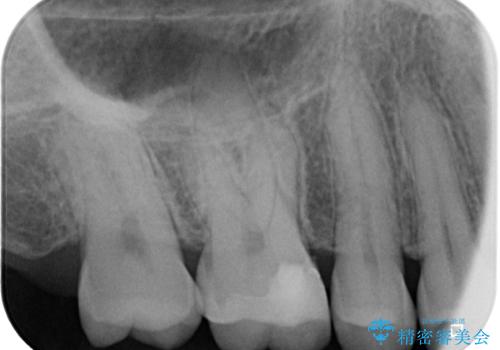

- 数年前他院にて治療した銀歯をやり替え希望の患者様です。

拡大鏡下で、銀歯、むし歯の除去を行い、セラミックインレーに適した形に整えました。

精度の良いインレーを製作するために、シリコーンにて型どりしました。